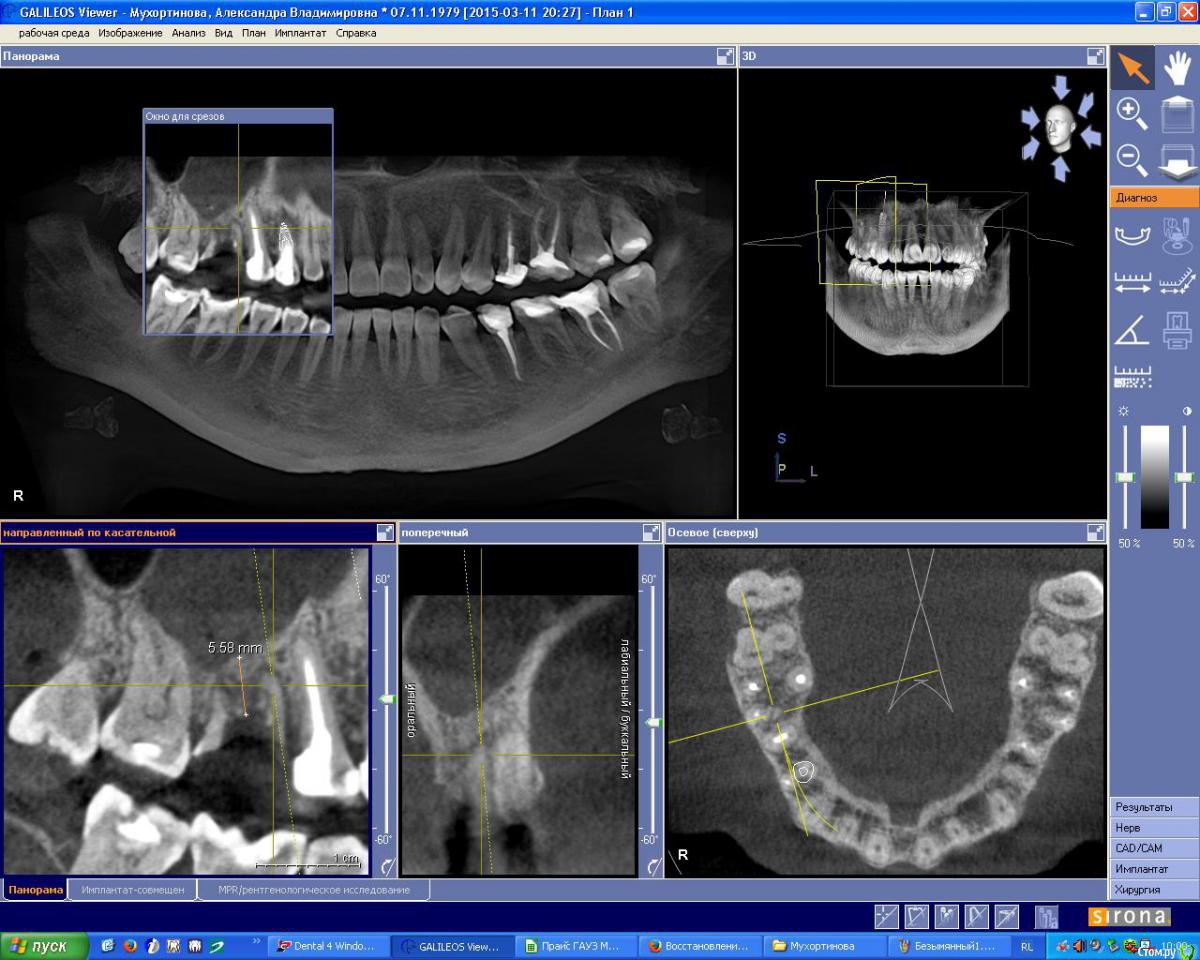

IshIm0 Опубликовано 8 июля, 2015 Поделиться Опубликовано 8 июля, 2015 (изменено) Добрый день. Пациентке Н. 2 недели назад ЛОР-врач удалил инородное тело из гайморовой пазухи справа (пломбировочный материал), который мигрировал в подглазничную область. Сейчас необходимо удалить зуб 16, пациентка хочет имплантат в последующем.Как всё правильно сделать ? Я думаю атравматично удалить зубик, аккуратно вычистить оставшийся пломбировочный материал в проекции дистально-щечного корня зуба 16 через лунку, подсыпать ксенокость, укрыть резорбируемой мембраной, через пол года установить имплантат в проекции 16 с одномоментным синус-лифтингом. Изменено 8 июля, 2015 пользователем IshIm0 Ссылка на комментарий

IshIm0 Опубликовано 8 июля, 2015 Автор Поделиться Опубликовано 8 июля, 2015 можно без графта вообще обойтись, можно любой вариант сопли в лунку зашить, можно соккет пресервейшн сделать. но если вы в любом случае намеренны делать синус, то я бы ограничился удалением и тонкой коллагеновой губкой поверх славного сгустка.Пожалуй так и сделаю, тем более посмотрел по КТ там в области бифуркации похоже кистогранулема притаилась. Ссылка на комментарий

OLG Опубликовано 8 июля, 2015 Поделиться Опубликовано 8 июля, 2015 есть кистогранулёма в бифуркации Нет там кистогранулемы в фуркациия вижу резорбцию костной ткани по бифуркации.обычно резорбция костной ткани в бифуркации сопровождается наличием грануляционной ткани или кисты. (см. снимки 1 и 2) 1 Ссылка на комментарий